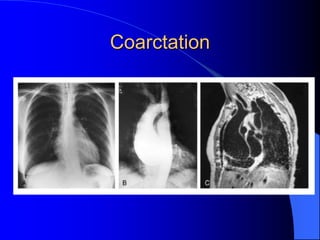

Coarctation CXR

 Increased collateral flow through the intercostal

arteries causes notching of the posterior third of

the third through eighth ribs

– Usually symmetric.

 Notching is not seen in the anterior ribs

– Anterior intercostal arteries are not located in costal

grooves

 The coarctation may be visible as an indentation

of the aorta with prestenotic and poststenotic

dilatation of the aorta, producing the “reversed E”

or “3” sign

Coarctation

Coarctation Imaging

 The coarctation may be visualized

echocardiographically

 Doppler examination can estimate

transcoarctation pressure gradient.

 Computed tomography, magnetic

resonance imaging, and contrast

aortography

– Location and length of the coarctation

– Visualization of the collateral circulation

– Measurement of Gradient on Cath

Coarctation CXR  Increasedcollateral flow through the intercostal arteries causes notching of the posterior third of the third through eighth ribs – Usually symmetric.  Notching is not seen in the anterior ribs – Anterior intercostal arteries are not located in costal grooves  The coarctation may be visible as an indentation of the aorta with prestenotic and poststenotic dilatation of the aorta, producing the “reversed E” or “3” sign

Coarctation Imaging  Thecoarctation may be visualized echocardiographically  Doppler examination can estimate transcoarctation pressure gradient.  Computed tomography, magnetic resonance imaging, and contrast aortography – Location and length of the coarctation – Visualization of the collateral circulation – Measurement of Gradient on Cath